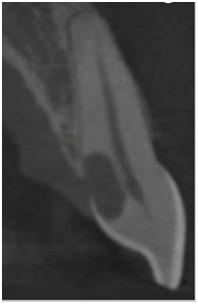

Wskaż prawdziwe stwierdzenie dotyczące zęba prezentowanego na załączonym zdjęciu RTG:

Obraz widoczny na zdjęciu CBCT przedstawia: